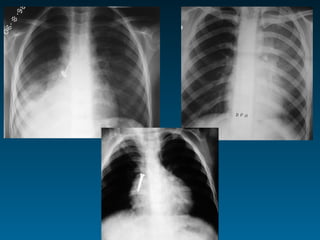

Οι συχνότερα χαμένες πνευμονίες